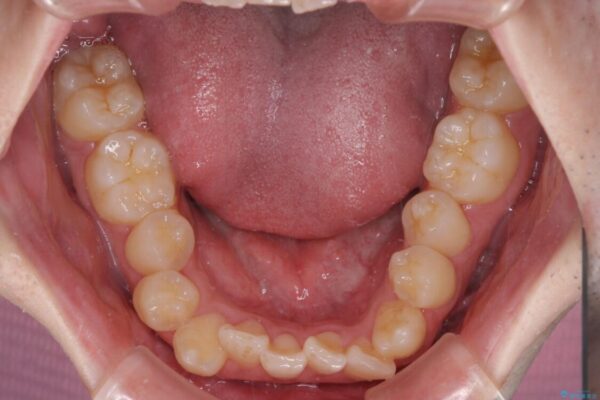

八重歯や奥歯の噛みにくさを気にして来院された患者様です。

前歯のクロスバイトや八重歯の他に、左右最後臼歯のシザーズバイト(鋏状咬合)が認められました。

治療前

• 全顎的なクロスバイト 補助装置を用いてワイヤー矯正 治療前画像